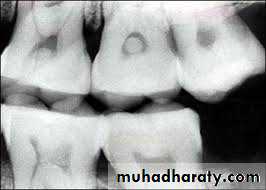

b. Hyperplastic form (pulp polyp) is overgrowth of granulomatous tissue into carious cavity.

• Hyperplastic form of chronic pulpitis is seen in teeth of children and adolescents in which pulp tissue has high resistance and large carious lesion permit free proliferation of hyperplastic tissue. Since it contains few nerve fibers, it is non-painful but bleeds easily due to rich network of blood vessels.

• Pain:It is usually absent.• Hyperplastic form shows a fleshy, reddish pulpal mass which fills most of pulp chamber or cavity. It is less sensitive than normal pulp but bleeds easily when probed.